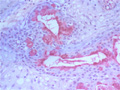

唾液腺腫瘍(粘表皮癌)

• 唾液腺腫瘍(粘表皮癌)ミクロ像(HE強拡大)